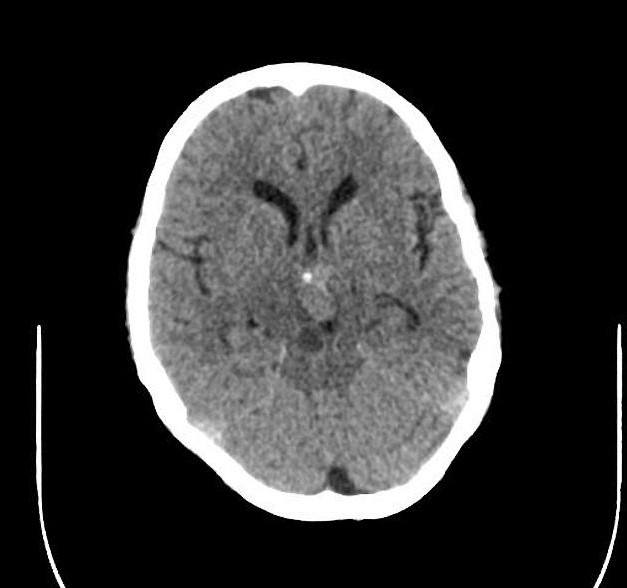

U sọ hầu

» Thông tin: Nam giới – 30 tuổi.

» Lâm sàng: Đau đầu.